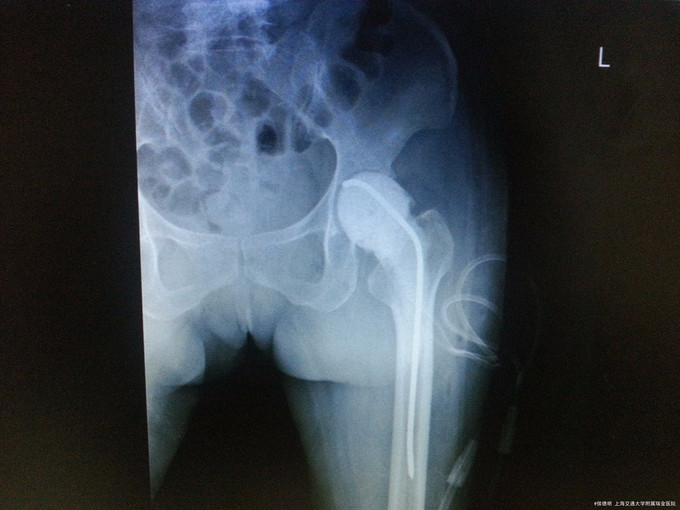

诊断:髋关节假体置入感染(左侧) 治疗:全髋关节感染翻修(髋关节假体取出+感染清创引流+spacer植入)

随访:术后患者血沉c反应蛋白明显下降。连续监测3月,指标稳定后可行翻修术。 讨论:关节置换术后感染常规可以采用2期翻修术。绝大多数患者能取得不错的预后。请讨论2期翻修术中应注意的问题